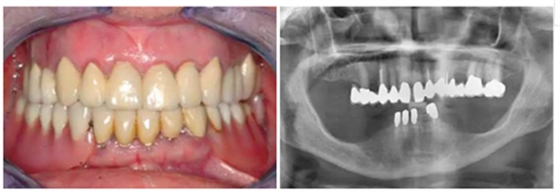

總的來說,72%的拔牙窩集中在上頜骨,而其中的63%是在前牙區(qū)(14-24)。(圖1a & b)

圖1a&b:SP或RP治療的拔牙窩的牙位分布。

有一位病人因為口腔鱗狀細胞癌而進行了部分舌和口底的切除術(shù),并進行了輔助放療。盡管由于組織的纖維化,外科準(zhǔn)備及創(chuàng)口縫合時變的非常困難,但患者的種植手術(shù)最終仍然成功了?;颊吲宕髁肆甑牧x齒,并且一直沒有出現(xiàn)問題。這部分的臨床過程及義齒情況詳見于圖8-18.